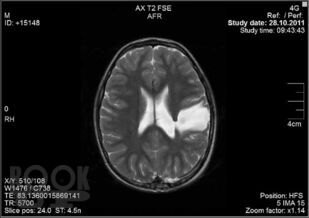

Монография посвящена актуальной проблеме современной неврологии – диагностике и восстановительному лечению детей с церебральным параличом, с использованием высокоэффективных способов медико-социальной реабилитации и психолого-педагогической коррекции когнитивных, психоэмоциональных и поведенческих расстройств. В работе представлен алгоритм клинико-неврологической, психологической и инструментальной диагностики когнитивных нарушений у больных детским церебральным параличом, а также подробно освещены наиболее используемые методы комплексного лечения, показана высокая эффективность инновационной методики – комплексной нейродинамической коррекции в восстановлении двигательных, сенсорных и когнитивных функций при детском церебральном параличе. Большое внимание уделено вопросам психологического сопровождения восстановительного лечения ребенка-инвалида с церебральным параличом, работе с семьей, организации социальной реабилитации, образования и профориентации. Книга рекомендована врачам-неврологам, психиатрам, педагогам, клиническим психологам, нейрофизиологам, логопедам, дефектологам, а также другим специалистам в области детской реабилитологии.